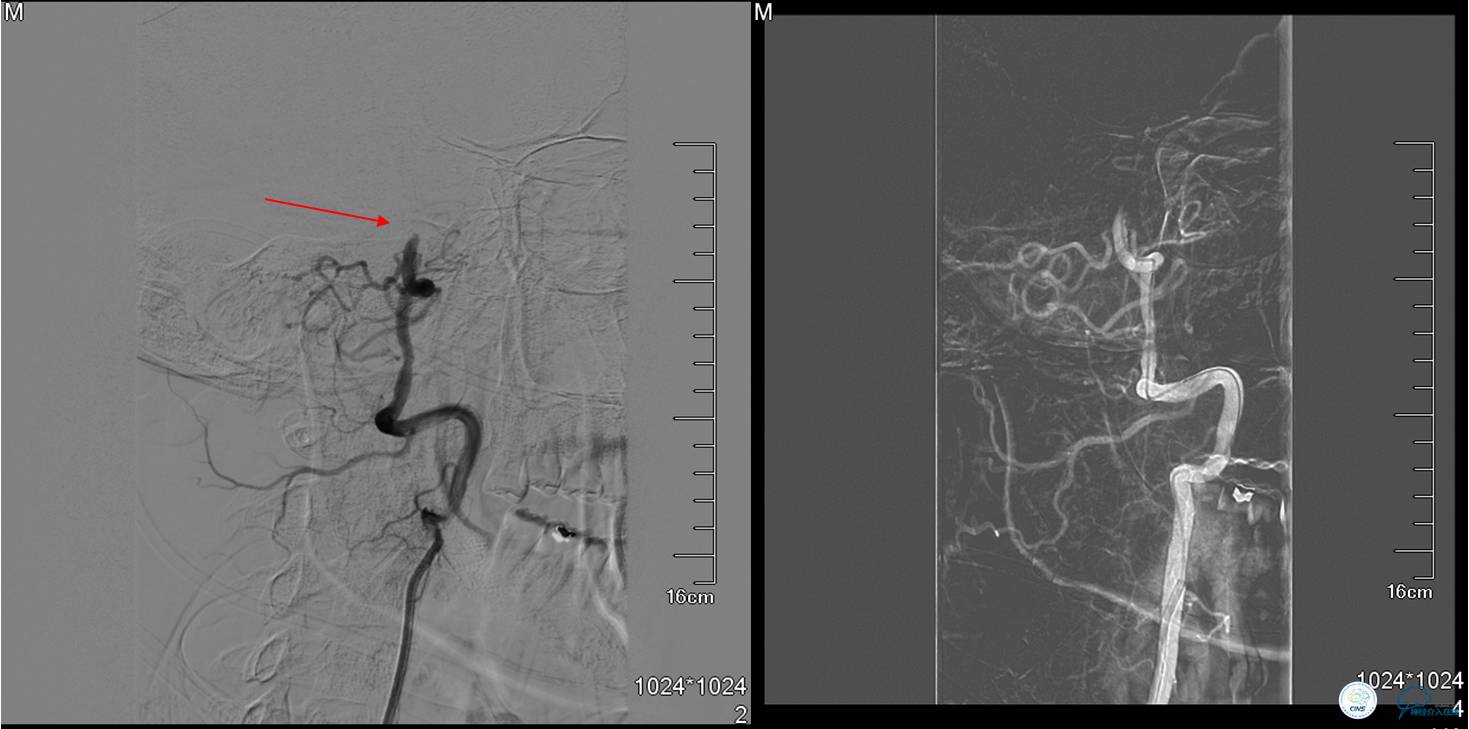

▼DSA:BA重度狭窄、右侧PCA开放。

DSA示TICI分级达到2b级(造影剂完全充盈,包括丘脑的供血,但排空延迟)。

▼DSA显示基底动脉再次闭塞。

▼支架取栓(Solitaire 6×30)后:血流恢复,仍存在严重狭窄。